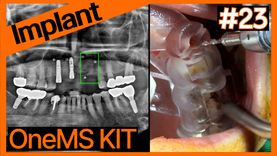

Full Mouth Implant Placement using OneGuide